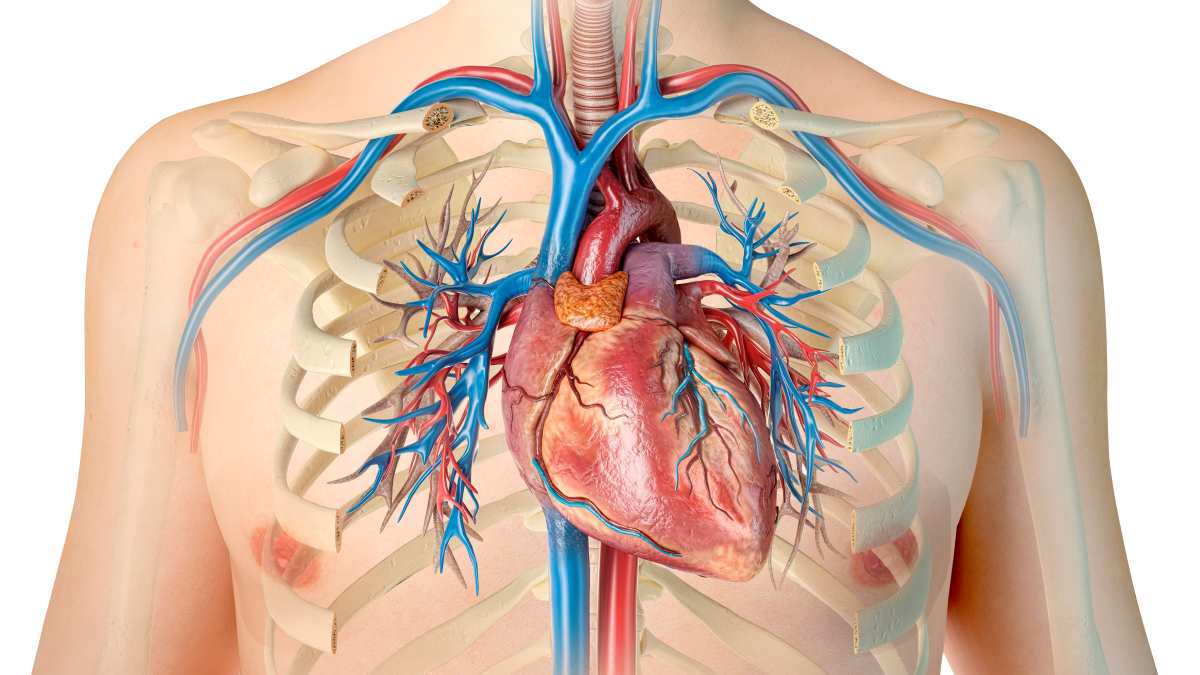

Анатомия Сердца: Расположение и Функции